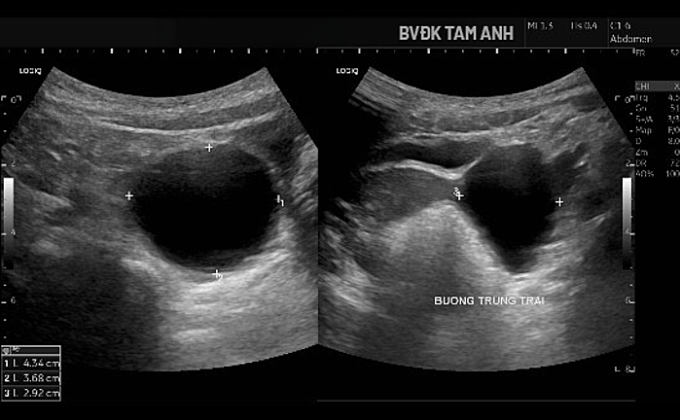

Ngoài ngực phát triển,bé Huyền chưa xuất hiện dấu hiệu dậy thì khác. ThS.BS Đỗ Tiến Sơn,khoa Nhi,Bệnh viện Đa khoa Tâm Anh Hà Nội,ghi nhận tuyến vú của trẻ đã phát triển ở giai đoạn Tanner B3 - giai đoạn bắt đầu xuất hiện mô tuyến vú nhanh và rõ. Buồng trứng trái có nang lớn kích thước khoảng 43x37x29 mm,thành mỏng,chứa dịch trong,bên trong có nang nhỏ. Tổn thương được xếp loại ORADS 2,nguy cơ ác tính thấp. Chụp MRI xác định nang buồng trứng trái lành tính. Kết quả X-quang đánh giá tuổi xương chưa tăng,hiện phù hợp với tuổi thực của bé.

Hình siêu âm cho thấy nang buồng trứng phì đại. Ảnh: Bệnh viện Đa khoa Tâm Anh